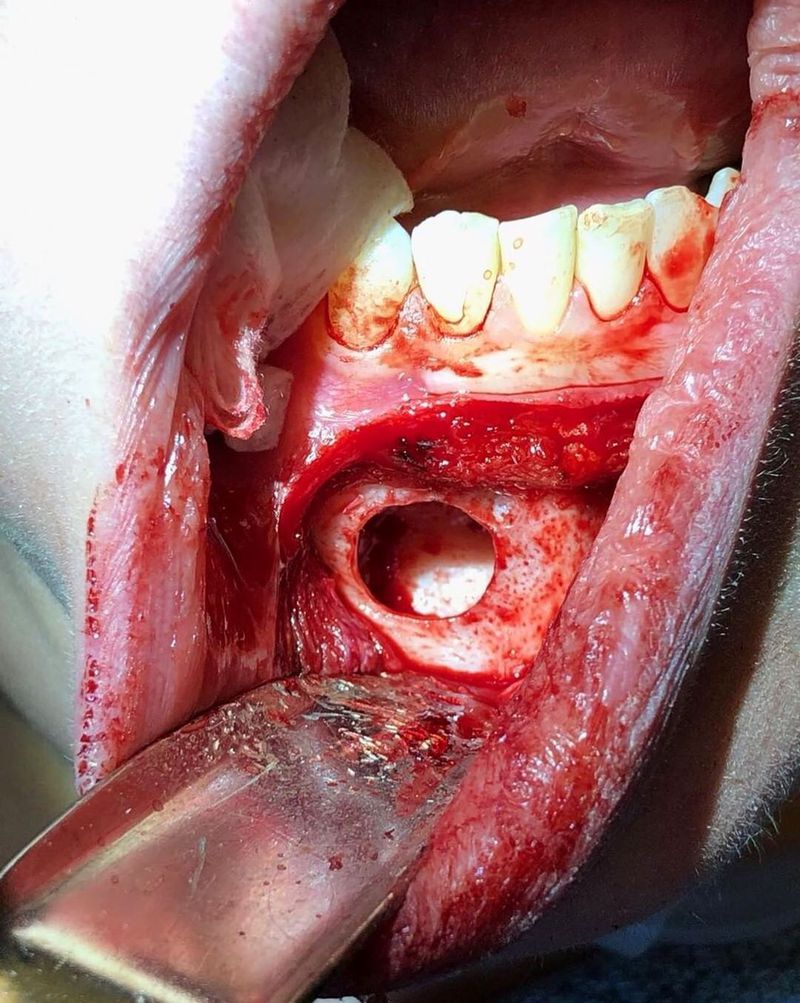

Is there any doubt that theres a hole in this lady's lower jaw? At this point, only the gum tissue was lowered down; no bone was removed. This lady had constant lower jaw pain, pressure and a sour taste in her mouth. This bone lesion went clear through her jaw into her oral cavity. She was diagnosed with a huge mandibular cystic lesion, which was treated with surgical cystectomy, resection of the involved bone, enucleation and decompression. Among these methods, enucleation after decompression is a conservative technique that decreases the size of the cystic cavity and reduces the risk of intra-bony defects, which could be induced by primary enucleation. Her surgery was difficult and she had minor nerve damage for a few weeks. But today, more than four years after the surgery, sheΓ’ΒΒs pain-free and no longer has a sour taste in her mouth.